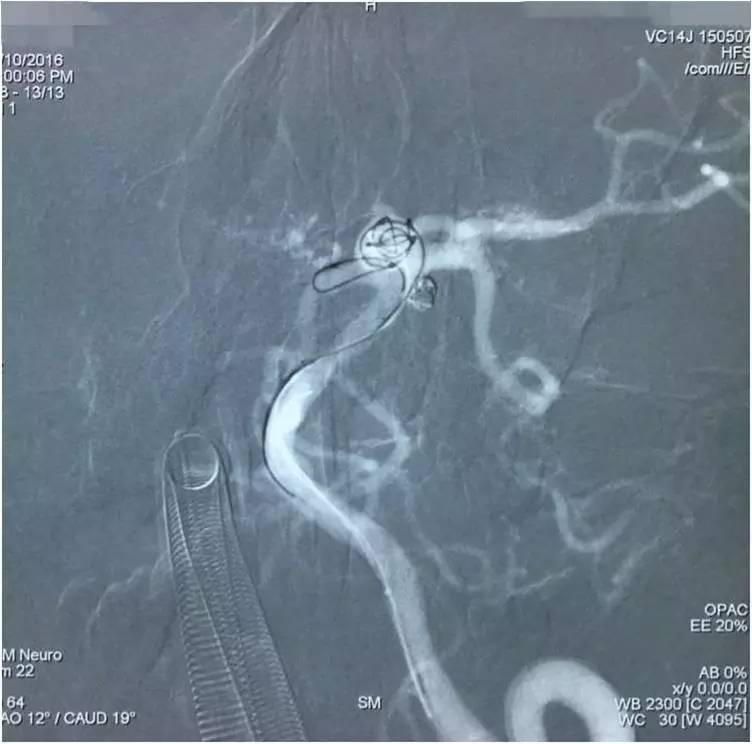

▼在Y型支架保护下经预置于瘤腔内的Echelon10微导管栓塞基底动脉顶端动脉瘤。

▼依次填圈,由于管头是朝向瘤腔右侧的,所以弹簧圈主要聚积在瘤腔右侧。

▼瘤腔左侧部还有空虚。

▼用微导丝将Echelon10的管头调整到瘤腔左侧空虚处继续“填空”。

▼瘤腔左侧部的空虚被填实,从整体看填塞的效果还是不错的。

▼然而,意外的是,造影评估显示动脉瘤顶端的子瘤还显影。